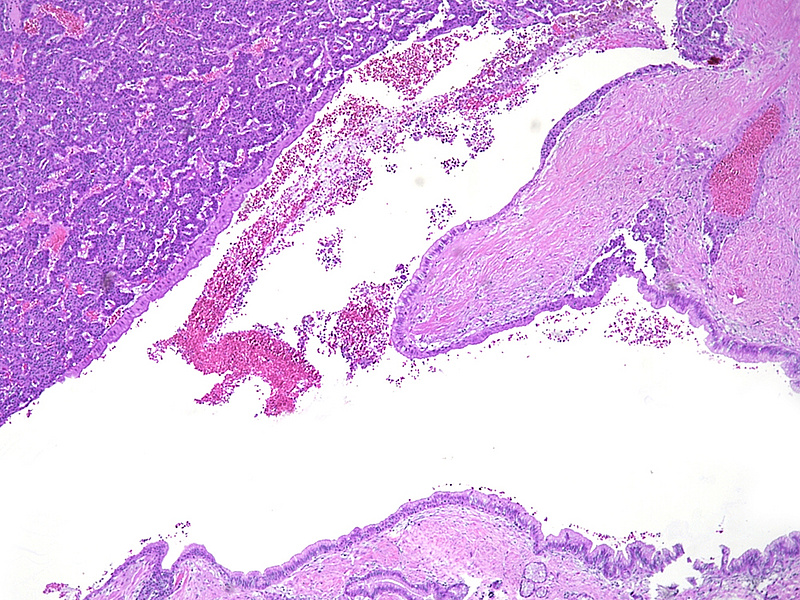

Upon magnetic resonance imaging (MRI) the pancreas contains several cystic lesions plus one partly solid, partly cystic lesion with a maximum diameter of 15 mm within the body. This lesion shows a biphasic pattern (Panel A). There are cysts lined by mucin-producing columnar cells with low grade dysplasia, consistent with a diagnosis of intraductal papillary mucinous neoplasm (IPMN). Other parts show a mainly solid, but also pseudoglandular growth of cuboidal cells with eosinophilic granular cytoplasm and centrally placed nuclei with “salt and pepper” chromatin and small nucleoli (Panels B-C). Mitoses are not detected. The two components merge with each other (Panel D), and in some foci the eosinophil granular cells underline the columnar cells (Panel E). The solid tumour component is strongly positive for synaptophysin (Panel F) and chromogranin A (Panel G), as are the underlining cells within the cystic component (Panel H). The Ki67 proliferation rate is low in the columnar epithelium (Panel I) and even lower (4%) in the solid component (Panel J). It is of note that the cells within the solid component express glucagon, while the cyst-lining mucus-producing cells are negative (Panels K-L).